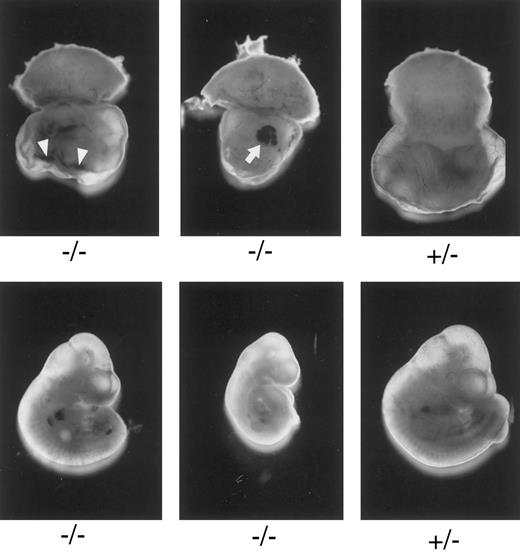

Macroscopic examination of E10.3 embryos. TFPIK1 genotypes are indicated. Arrowheads, intra-yolk sac hemorrhage with red blood cells in yolk sac folds; arrow, blood “lakes” in yolk sac. Note that yolk sac hemorrhage can be found with a near normal embryo (left, bottom), suggesting that hemorrhage and concomitant circulatory collapse precede the wasting and ultimate death of the embryo.

Characterization of TFPIK1(−/−) mice.Of 233 pups born following the mating of heterozygotic TFPIK1(+/−) mice, 35% were TFPIK1(+/+) and 65% were TFPIK1(+/−) (Table 1). To examine the phenotype of TFPIK1(−/−) mice, embryos were collected at various times of gestation after matings between TFPIK1(+/−) mice. TFPIK1(−/−) embryos were indistinguishable from TFPIK1(+/−) and TFPIK1(+/+) at embryonic day 8.5 (E8.5) (data not shown). Between E9.5 and E11.5, however, many of the TFPIK1(−/−) concepti displayed intra-yolk sac hemorrhage and a paucity of blood in yolk sac vessels (Fig 2). The embryos contained within these yolk sacs were usually pale and growth retarded, and occasionally had pericardial effusions containing extravasated red blood cells.

The earliest abnormalities observed with TFPI deficiency are the yolk sac hemorrhage and loss of blood in the yolk sac vasculature which are detectable at E9.5. These changes are usually found in association with a pale embryo with severe growth and developmental retardation. Yolk sac hemorrhage can be found with a near-normal embryo (Fig 2), however, suggesting that hemorrhage and concomitant circulatory collapse precede and lead to the wasting and ultimate death of the embryo. The extent of the histological yolk sac abnormalities appears to mirror the condition of the embryo, suggesting that the embryonic and extra-embryonic tissues of these TFPIK1(−/−) concepti are responding to the same insult (Fig 3). The blood “lakes” (Fig 2) and thin acellular septae connecting the visceral endoderm and mesoderm of the yolk sac (Fig 3D) that are found in TFPIK1(−/−) concepti have also been noted in TF-deficient embryos,21 but the TF activity of TFPIK1(−/−) whole embryos and their derived embryonic fibroblasts is equivalent to that of TFPIK1(+/+) animals (data not shown).